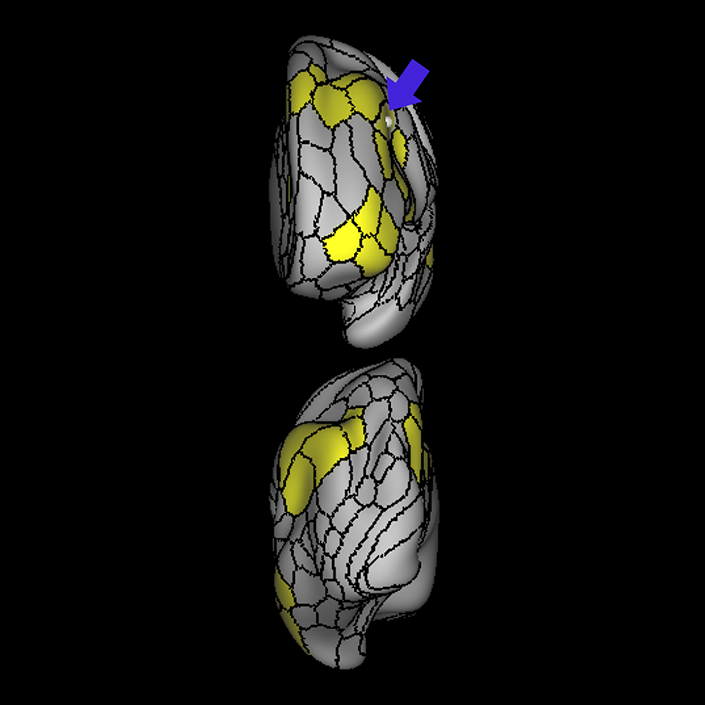

ᐅ SummaryArea 44: part of the inferior frontal gyrus of the lateral frontal lobe. Translates abstract and intentional information in the prefrontal cortex to more detailed representations to help guide the production of verbal and manual actions. In addition to its known association with Broca's area, is sometimes represented as part of Broca's complex ᐅ Where is it?Area 44 is at the posterior most part of the inferior frontal gyrus. It is the anterior bank of pars opercularis of the IFG. ᐅ What are its borders?Area 44 borders area 45 anteriorly and area 6r posteriorly. Area 8C is its medial border and its inferior border is wedged between then upper borders of Areas 6R and 6V. Its superior edge borders IFSp and IFJa. Its opercular surface is FOP4. ᐅ What are its functional connections?Area 44 demonstrates functional connectivity to areas SFL, IFSp, IFJa, 45, 47s, 47L, 9a, 9m, 8AV, 8BL and 8C in the dorsolateral frontal lobe, area 8BM in the medial frontal lobe, area 55b in the premotor areas, areas FOP5, AVI and PSL in the insula- opercular region, areas TGd, STSdp and STSvp in the temporal lobe, areas PFm, and PGi in the inferior parietal lobe, and no areas in the medial parietal lobe. ᐅ What are its white matter connections?Area 44 is structurally connected to the arcuate/SLF and the FAT. Connections with the arcuate/SLF project posteriorly and wrap around the Sylvian fissure to the middle temporal gyrus to end at TE1a and TE1m. There are also projections from the arcuate/SLF before it terminates to parcellations A5 and STSdp. The majority of the inferior connections of the frontal aslant tract end at 44, the tract is connected superiorly to superior frontal gyrus parcellations SFL, 6ma and s6-8. Local short association bundles are connected with 45 and 8C. White matter tracts from 44 in the right hemisphere have less consistent connections with the arcuate/SLF. ᐅ What is known about its function?Area 44 translates abstract and intentional information in the prefrontal cortex to more detailed representations to help guide the production of verbal and manual actions. Area 44, in addition to its known association with Broca's area, is sometimes represented as part of "Broca's complex", including Brodmann Areas 45, 46, 47 and the mesial supplementary motor area of 6, which contribute to a frontal-subcortical circuit. The right pars opercularis has also been implicated in cognitive inhibition in the overall context of working memory. |

A: lateral-medial

B: anterior-posterior

C: superior-inferior

DTI image |